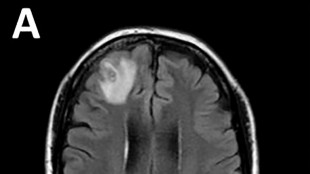

Médicos australianos hallan por primera vez una lombriz parásita en el cerebro de una mujer

Una lombriz parásita usualmente encontrada en serpientes fue retirada "viva y coleando" del cerebro de una mujer, algo que no se había visto en los registros médicos, informaron el martes médicos australianos.